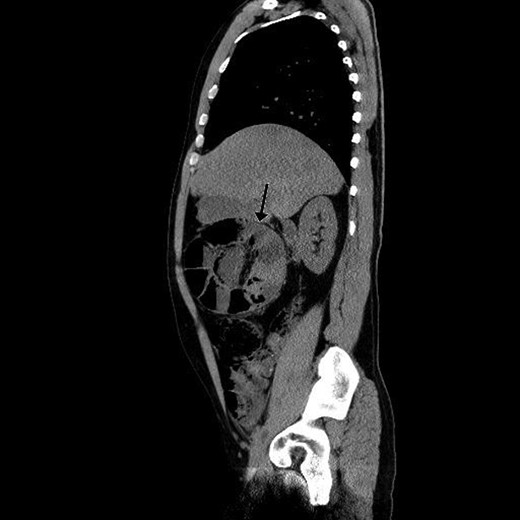

Paraclinical tests showed leucocytosis (10,1 × 109/l) and normal serum lactate. A computed tomography (CT) scan showing gastric retention, encapsulated dilated small intestines in the right upper quadrant with pneumatosis intestinalis and collapsed small intestines distally from this area interpreted as intestinal obstruction (Figs 1 and 2).

Sagittal view of preoperative abdominal CT scan demonstrating encapsulated dilated small intestines in the right upper quadrant with pneumatosis intestinalis.